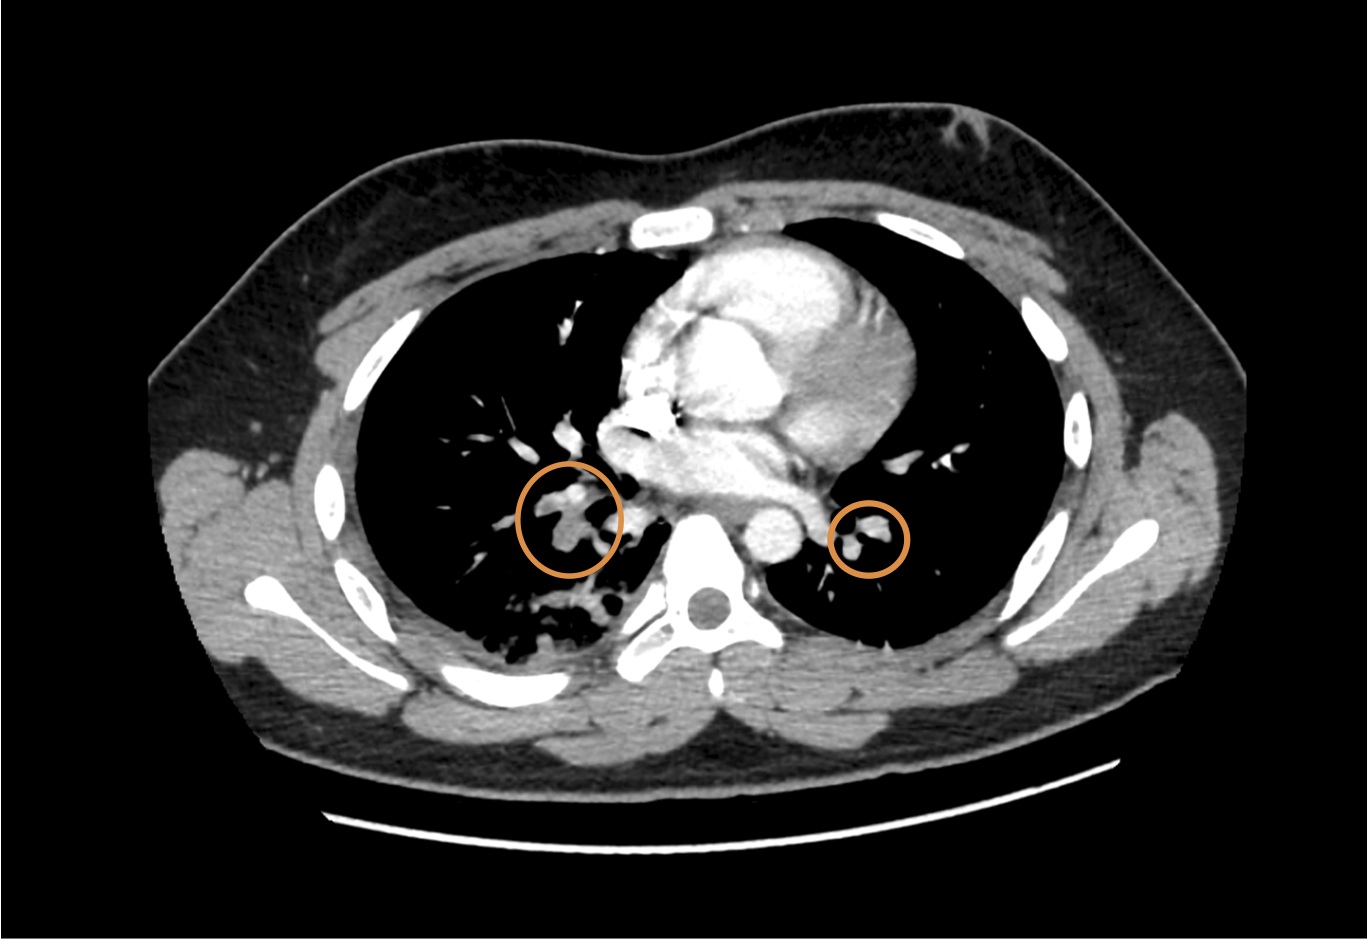

Figura 1. Angio-TC del torace: embolia polmonare non massiva bilaterale.

Alla luce del rilievo anamnestico, della persistenza della sintomatologia dolorosa con tendenza all’immobilità del torace e respiro sempre più superficiale nonostante terapia antidolorifica per via endovenosa, nel sospetto di embolia polmonare, viene eseguita angio-TC del torace con conferma della diagnosi: presenza di focali difetti di riempimento tromboembolici a carico dell'arteria polmonare per il lobo inferiore di destra e a carico delle diramazioni a valle, alcuni piccoli focali difetti di riempimento a carico dei rami arteriosi per i segmenti postero basali del lobo inferiore di sinistra. Presenza di consensuale addensamento parenchimale.

Il nostro paziente ha presentato una EP non massiva, segmentaria destra e minima a sinistra, insorta 4 giorni dopo intervento di ablazione transcatetere del fascio di conduzione accessorio in sindrome di Wolff-Parkinson-White. È necessario porre sempre un’attenzione particolare al dolore toracico e alle varie diagnosi differenziali: nel caso di embolia polmonare il solo sospetto clinico, correlato a un’accurata anamnesi, pone indicazione a immediato approfondimento strumentale con angio-TC (Figura 1)3. La scarsa specificità dei sintomi e l’assenza di uno score validato da utilizzare nel sospetto clinico di EP, rendono difficoltosa la diagnosi precoce; pertanto il sospetto clinico, fondato sul riscontro anamnestico dei fattori di rischio noti, rappresenta in età pediatrica il maggior elemento di forza nel processo diagnostico.